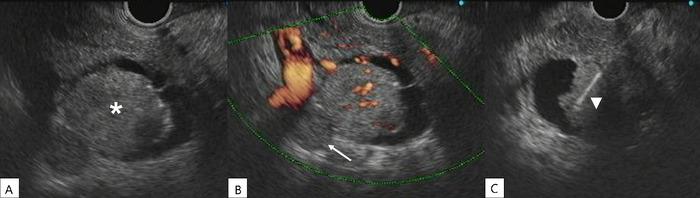

CASE REPORT

We report the case of a patient who developed a pancreatic metastasis from a classic variant papillary thyroid carcinoma 11 years after total thyroidectomy, cervical lymphadenectomy, and radioactive iodine ablation. The patient experienced increased thyroglobulin levels, and abdominal computed tomography scan revealed a lesion in the uncinate process of the pancreas. Tissue samples obtained by endoscopic ultrasound-guided biopsy were positive for thyroglobulin and thyroid transcription factor 1. Because the patient was not a candidate for surgery, the metastatic lesion was not iodine-avid, and tyrosine kinase inhibitors could not be offered because of tumor-related symptoms, the patient was treated with stereotactic body radiotherapy only. The patient died almost 2 years after the diagnosis of metastatic papillary thyroid carcinoma to the pancreas (13 years after total thyroidectomy for the primary cancer).

我们报告一例患者,在全甲状腺切除、颈部淋巴结清扫及放射性碘消融术后11年,出现了源自经典型乳头状甲状腺癌的胰腺转移。患者甲状腺球蛋白水平升高,腹部计算机断层扫描显示胰腺钩突部有一病灶。经内镜超声引导下活检获取的组织样本甲状腺球蛋白和甲状腺转录因子1呈阳性。由于该患者不适合手术,转移病灶不摄取碘,且因肿瘤相关症状无法使用酪氨酸激酶抑制剂,故仅对患者进行了立体定向体部放疗。该患者在被诊断为胰腺转移性乳头状甲状腺癌后近2年死亡(距原发癌全甲状腺切除术后13年)。